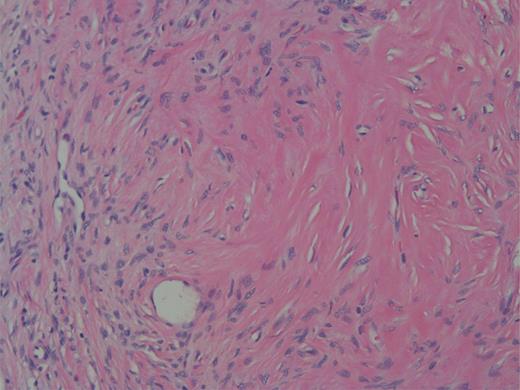

The specimen was a 3.5 ×3 ×3-cm white, firm, well-circumscribed mass located in the head of the pancreas (Fig. 3). The mass was found to be compressing the distal aspect of the main pancreatic duct. All 15 lymph nodes received in the specimen were negative. Histologically, the tumor is well circumscribed from normal pancreatic tissue and composed of spindle cells that in some areas form short ill-defined fascicles and in other areas are randomly arranged in a dense fibrohyaline stroma. A well-developed vascular network was visualized throughout the tumor with vessels of a stag horn appearance with thin hyaline wall and tumor growth around (Figs 4 and 5). No significant mitotic activity or tumor necrosis was noted. Immunostaining was positive for CD34 (Fig. 6) and BLC-2; focally for B-catenin, and focally weak staining for CD99, compatible with fibroblastic origin. The tumor cells were negative for the following cell markers: CD117, CAM5.2, AE1/AE3, EMA, synaptophysin, chromogranin, CD56, PR, SMA, Desmin, S100, MelanA and HMB45. The M1B1 proliferation index was low (<5%). These findings in combination are consistent with a SFT.

High power showing spindle cells of minimal nuclear pleomorphisms.